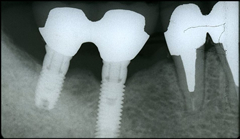

インプラントを埋入する部位の歯肉を開き、顎の骨にインプラントを埋入します。インプラントが骨にしっかり結合するまで約3ヶ月程度待ちます。 この間、必要に応じて仮歯を入れることもできますので、日常生活に差し支えありません。